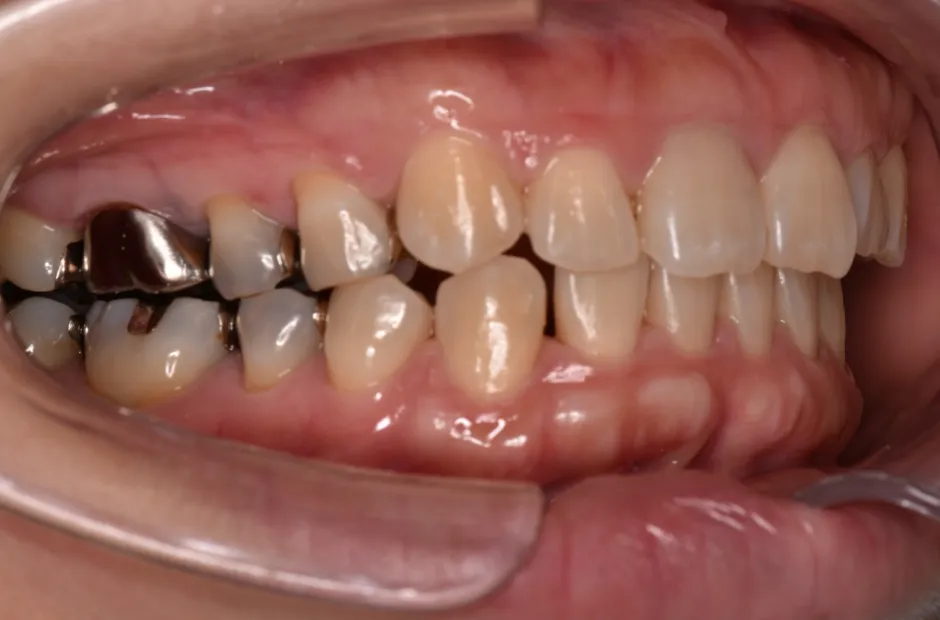

叢生

| 診断名・主訴 | 叢生 |

|---|---|

| 年齢・性別 | 43歳・女性 |

| 治療期間・回数 | 2年7か月 27回 |

| 治療に用いた主な装置 | 舌側矯正 |

| 抜歯部位 | 両顎4,4 |

| 治療費 | 100万円(税抜) |

| リスク・副作用 | 装置による違和感・疼痛・歯肉退縮・歯根吸収・虫歯のリスクなど |